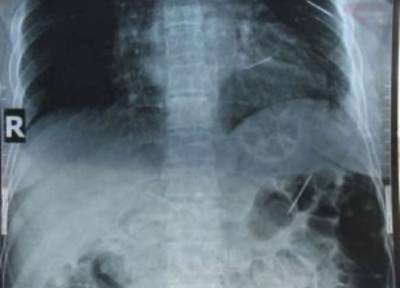

وقالت الصحيفة أن الأطباء عثروا في جسم آلاتان هاسيا على 9 دبابيس، مفرقة في كل من الرئة والكلى والكبد والساق وعلى مقربة من القلب، بعد إجرائها أشعة سينية.

وقالت «هاسيا» من جارود بانر في شمال الصين، أن زوجها السابق اعتاد ضربها، وبعد هجرها له في 2002، جاء إليها في بيت أهلها وضربها حتى دخلت في غيبوبة، وعندما أفاقت وجدت بجانبها على الأرض دبابيس وإبر قام زوجها بإدخال بعضها في أنحاء متفرقة بجسدها.